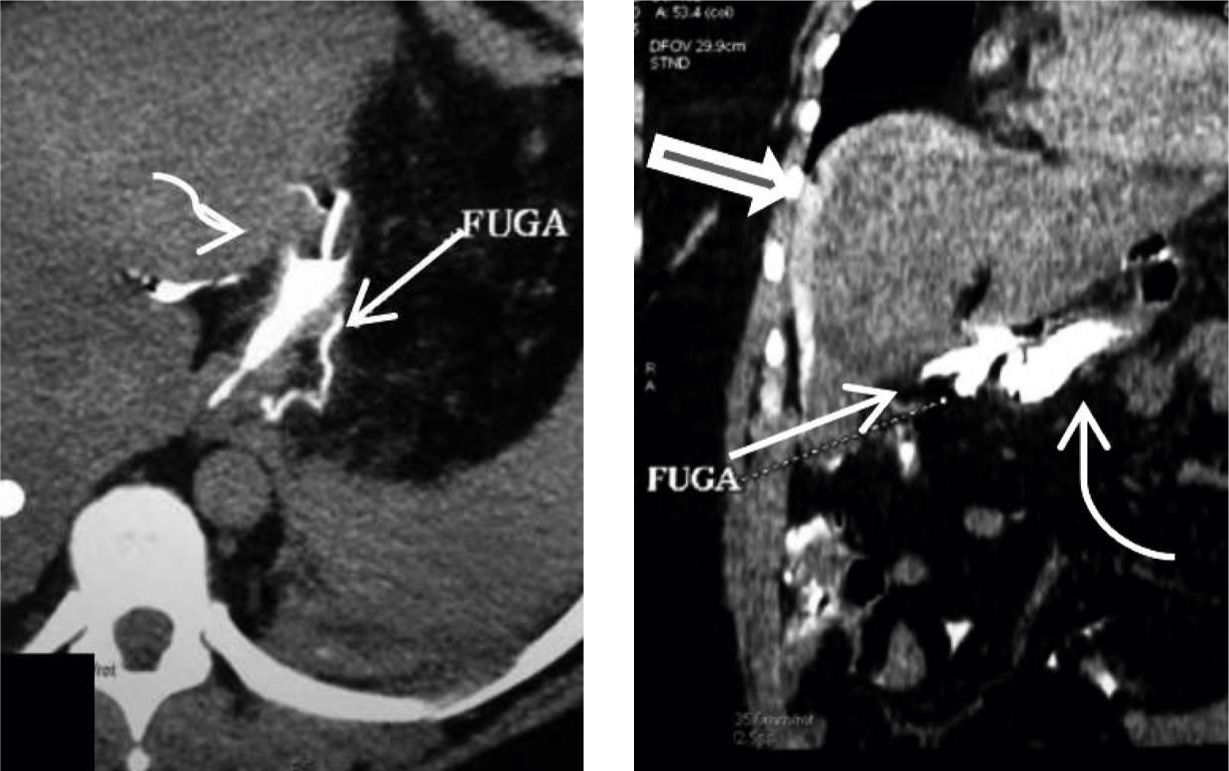

Figura 3

a) Corte axial

b) reconstrucción coronal de TC

sin medio de contraste endovenoso, donde se visualiza la GM con contraste positivo intraluminal (flechas curvas), fuga de contraste adyacente a la misma (flecha fina) y a nivel perihepático (flecha gruesa).

Según el tiempo de presentación se dividen en: precoces (1-4 días del postoperatorio), de etiología mecánica y tardías (más de 4 días), de etiología isquémica (6). Figura3 (a y b).

b) Colecciones y abscesos Las colecciones y los abscesos usualmente se producen como consecuencia de fugas. La TC con contraste i/v es el estudio de elección. Los abscesos se presentan como una lesión bien definida, hipodensa, es avascular, uni o multilocular (signo del acúmulo o cluster), con realce periférico y de los septos tras la administración del medio de contraste i/v. A veces contienen líquido, gas y/o niveles hidroaéreos, la presencia de contraste oral en su interior orienta a fístula. En general se topografían en el cuadrante superior izquierdo, más frecuentemente en el espacio subfrénico (6,7,10). FIGURA 7

con medio de contraste i/v, sin contraste oral observándose un absceso a nivel subfrénico izquierdo (flecha fina) y escaso derrame pleural del mismo lado (flecha gruesa)(Paciente Nº 6)